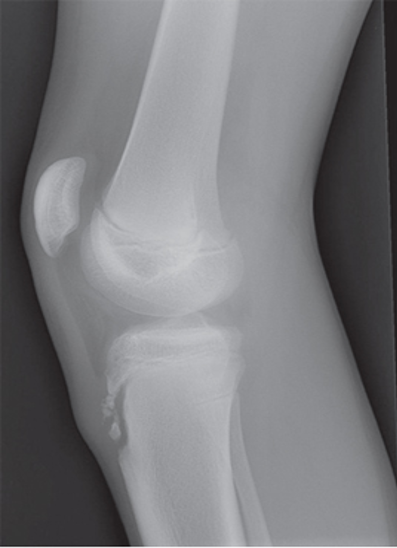

osteoarthritis (degenerative joint disease)

generalized disorder pathologically characterized by loss of joint cartilage & reactive new bone formation

traumatic, stress to joint

what is the casue of osteoarthritis?

advance stage → subtractive disease

what is the technique for a osteoarthritis?

pt w/ osteoarthritis

what is this image?